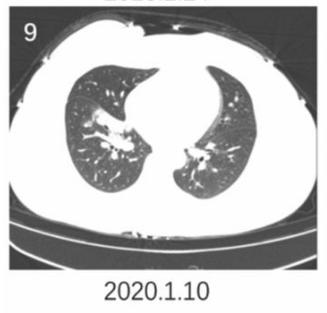

再来看这个新冠肺炎患者,磨玻璃阴影内有清晰的网格状阴影,类似铺路石征。

图9